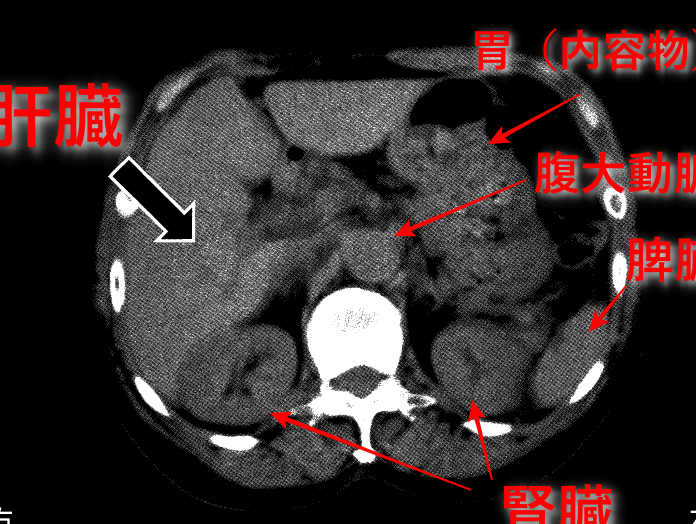

腎臓は、人体にとって必要不可欠な器官であり、様々な重要な機能を持っています。腎臓の主要な役割を理解することは、健康を維持する上で重要です。

腎臓は、体内の水分量を調整しています。水分が不足すると、腎臓は尿の生成を減少させて体液を保持します。一方、体液が過剰な場合、尿を多く排出して過剰な水分を取り除きます。この調整機能は、血圧の維持にも関与しているため、正常な体の機能をサポートします。